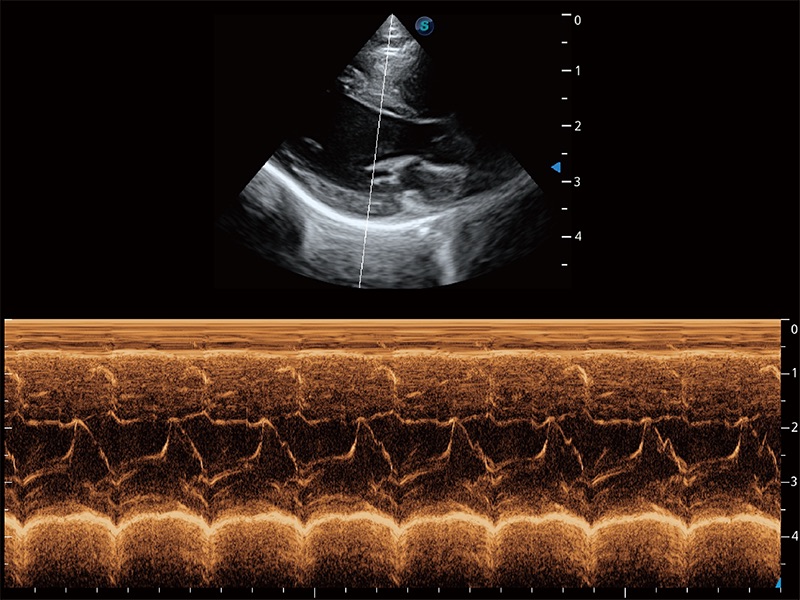

ProPet 80 配备了丰富的心脏探头群、先进的成像技术和专业的心脏测量工具,可帮助动物医生为不同体型和生理结构的动物提供心脏和心肌功能的全面评估。

实时用颜色表示心肌组织运动,观察和定量组织的运动情況,对快速检测与评估心肌的灌注和活性、电传导及心肌收缩和舒张功能等均能提供重要的诊断信息。

通过360度任意调节3条M型取样线,在同一心动周期上观察心脏不同位置的运动曲线,得到准确的心功能测量数据,有效评估心肌运动及左心室功能。

能够基于左心室壁追踪和辛普森法,自动计算射血分数,支持多个可移动点描迹,与手动测量相比,极大节省了动物医生的时间和精力。